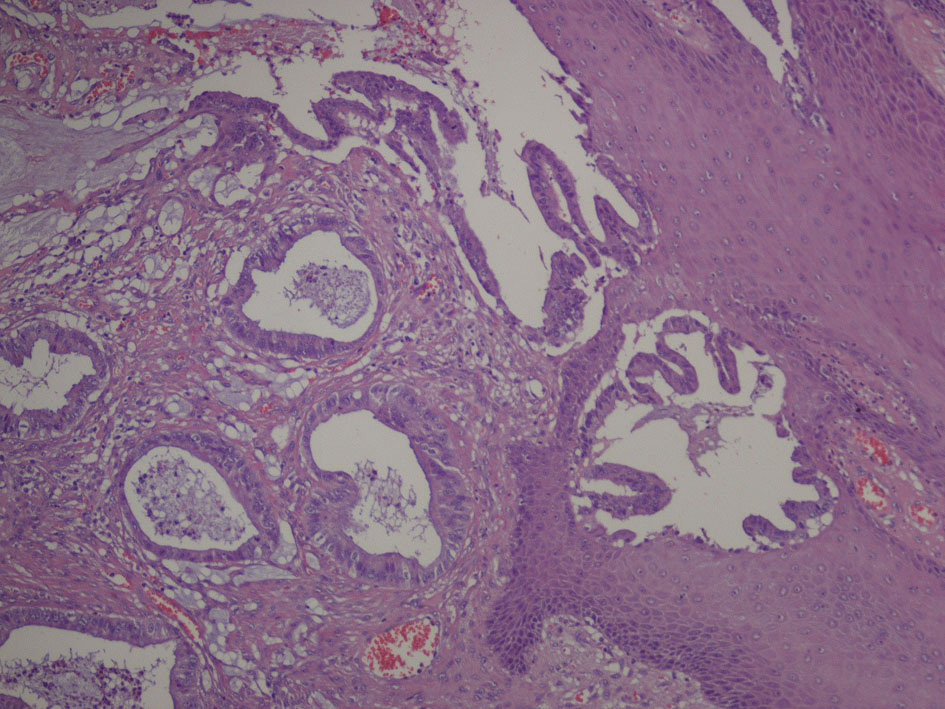

We decided to perform a surgical resection of the scrotal mass. We removed a 10 cm skin flap with underlying soft tissue and epidermal ulcerative lesions. Subcutaneous tissue presented cystic aspects with clear mucinous material. Microscopically (Fig. 4, 5), cysts consist of atypical epithelial columnar cells with mucinous citoplasm, some goblet cells, forming abnormal ectasic glandular structures and abundant extracellular mucus.

![]() Click for large image | Figure 4. Microscopic image: cystic tumoral tissue with atypical cells and abundant mucin. |

Immunophenotype was: cytocheratine 20+, CDX2a+, cytocheratine 7-, WT1-, negative estrogen and progesteron receptors; stromal and vascular invasion was observed (Fig. 6, 7).

Histological diagnosis was mucinous adenocarcinoma with medium grade differentiation. Differential diagnosis was between a primitive mucinous paratesticular cancer “ovarian-type” and metastasis of gastrointestinal cancer, specifically of cecum or right colon. Pathologist suggested performing further investigation.